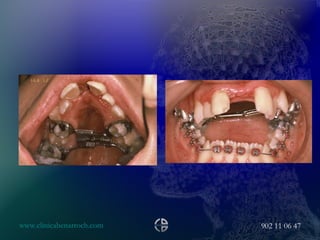

LR, F, 21.July, 2000 PROBLEM LIST Ocular surface disease Nasal deformity Lower third vertical augmentation Upper and lower lip deformity Maxillary transverse collapse AP chin deficiency Vertical chin augmentation SURGICAL PLAN 2 PHASES Maxillary assisted expansion Maxillary posterior impaction Mandible BSS Lip pasties Vertical reduction of the chin AP chin advancement

• #79 Maxillary assisted expansion with the same protocol of the last case, the orthodontics star to move the central incisors after 4 months

• #80 10 month after de expansion